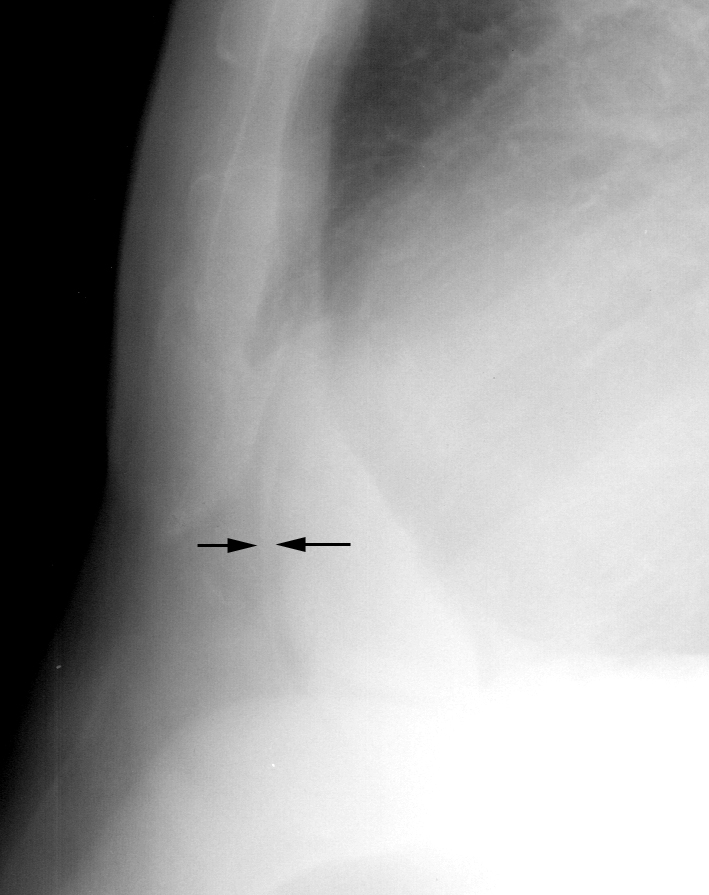

Peric stripe - slightly thickened close up

Peric stripe - slightly thickened

close up